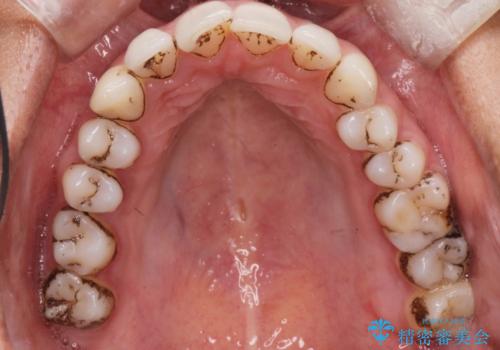

着色が気になる(エアフロー)

- 着色が気になるとの事で来院。

エアフローでしっかり着色を取り除きました。

着色が目立たなくなり大変満足して頂けました。